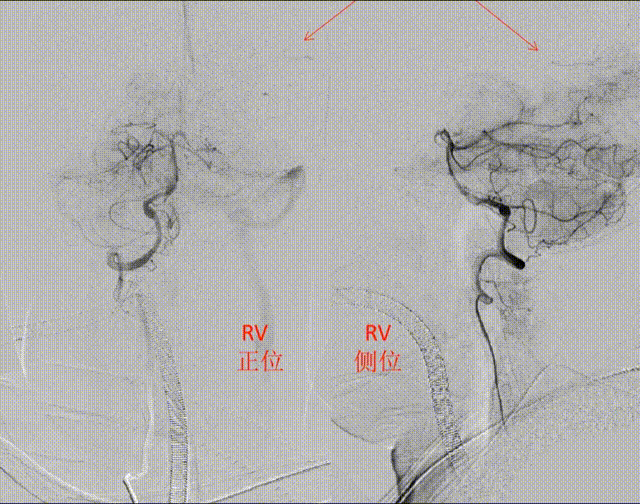

ASITN/SIR 1级-

STIFF导丝指引,NeuronMax长鞘连接抽吸泵,持续最大负压下缓慢进入C1中段。

轻推造影剂观察

直接微导管到位造影

ET2支架释放后造影,明确远端血栓位置和负荷

相信ET2支架的抓栓能力,没有盲交换上大口径的抽吸导管。

释放支架过程中,没有采用传统的直接脱鞘技术,而是采用支架微导丝、微导管给张力,类似EP2外弧释放技术,尽量在血管弯曲处均匀张开支架。

舍弃EPIC和SWIM技术,支架裸导丝、长鞘上高接近岩谷段并持续抽吸、利用ET2优势直接拉栓。

mTICI 2b

DPT50分钟,PRT26分钟